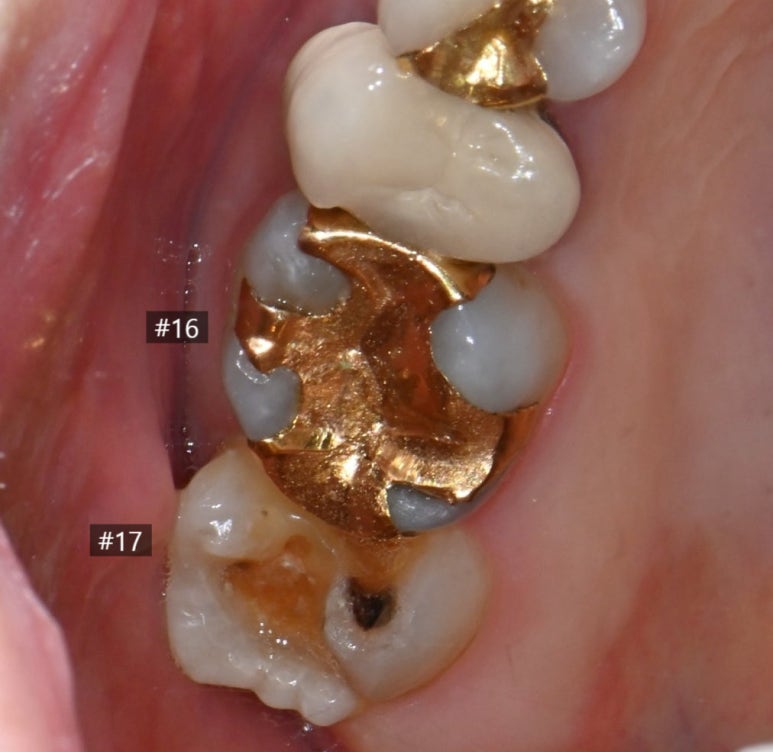

25.11.11 #17 치아의 금 인레이가 탈락하고 충치가 발생한 모습.

25.11.11 앞쪽 어금니(#16) 금 인레이 하방에서 발견된 충치

문제가 된 큰 어금니를 치료하던 중,

바로 앞쪽 어금니(#16)의 상태도

심상치 않음을 발견했습니다.

이 치아 역시 금 인레이가 되어 있었는데,

틈새로 비쳐 보이는 내부가

이미 충치로 오염되어 있었습니다.